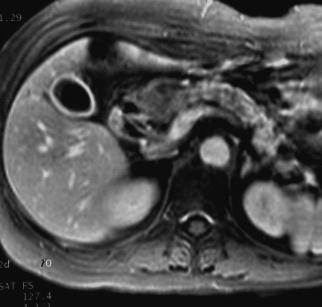

Cette femme de 78 ans est atteinte d'un cancer du pancréas révélé par un ictère nu.

L'I.R.M. est demandée dans le cadre du bilan d'opérabilité.

Découverte de plusieurs nodules de petite taille qui se rehaussent en couronne après injection de Gadolinium.

Séquences T1 avant et après Gadolinium

Bili IRM : Le nodule a un contenu liquidien très intense en T2 permettant de dire qu'il s'agit d'un hamartome kystique. Le diagnostic est confirmé à l'intervention.